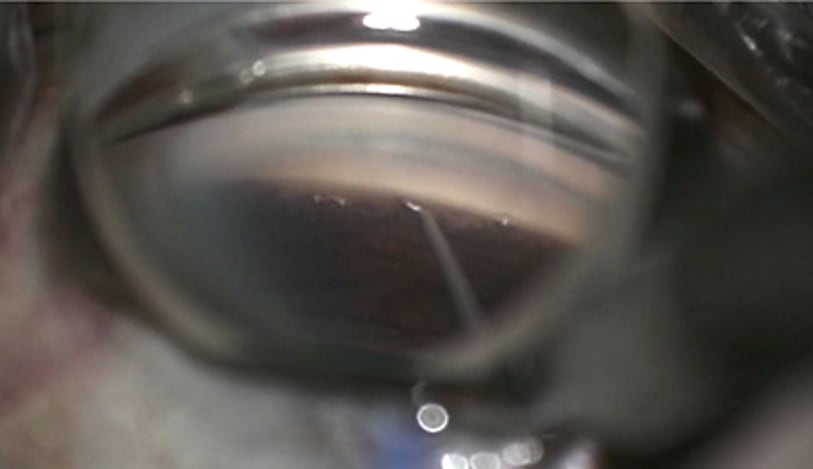

Laser-Titratable Shunt Shows Promise in Feasibility Study

March 19, 2025